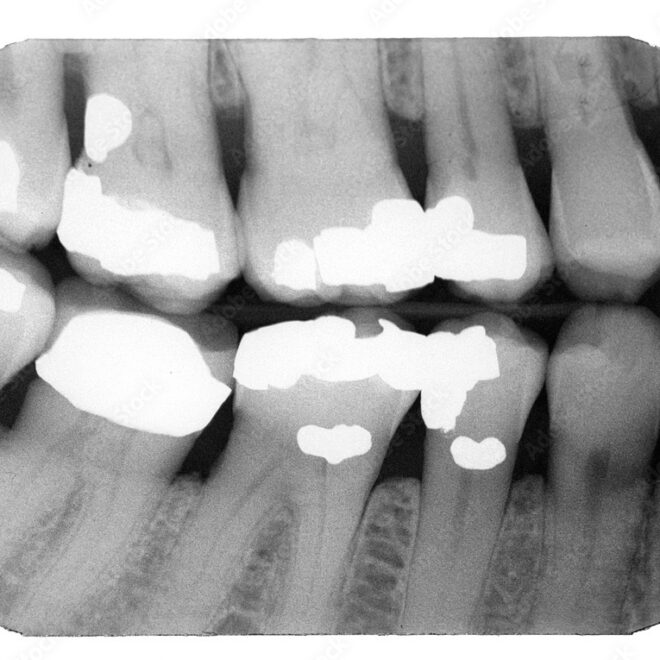

What Do Cavities Look Like on an X-Ray? Dental Images Decoded